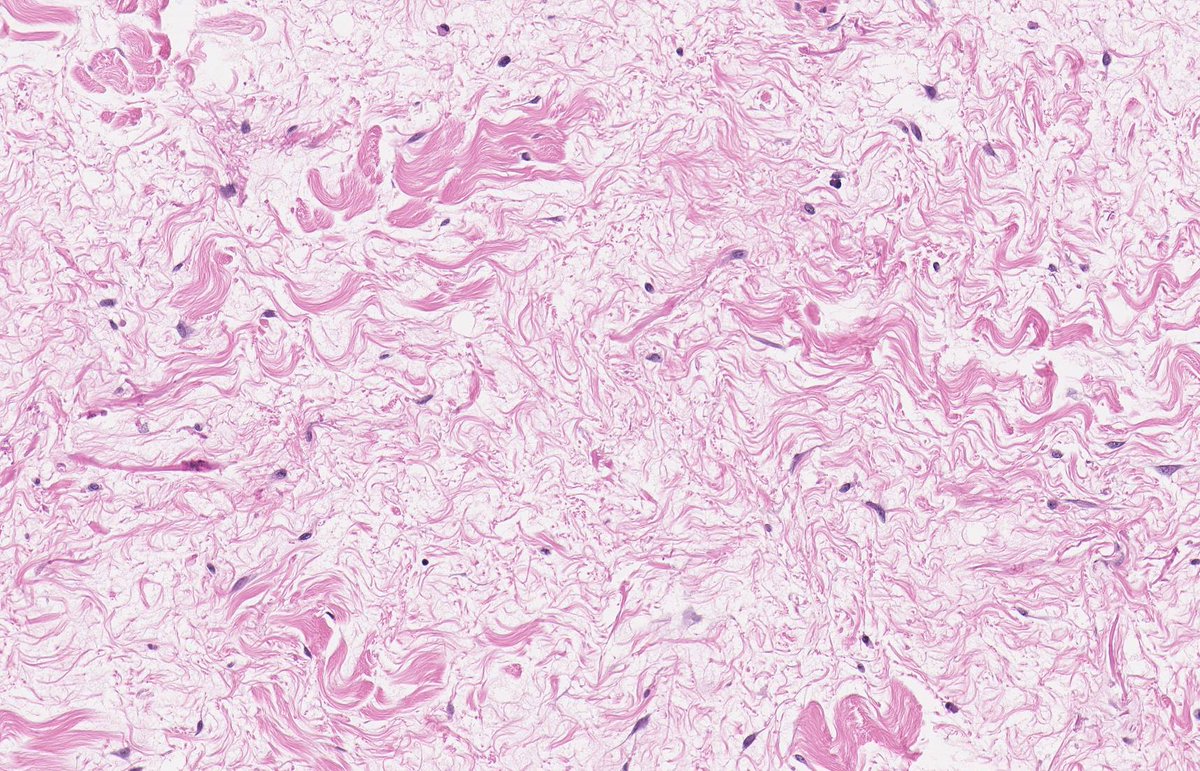

MASSIVE LOCALIZED LYMPHOEDEMA. NB: lobules of mature adipose tissue; expanded interlobular septa; spindle-stellate cells with mild atypia and prominent myxoid background; ectatic lymphatic spaces; MDM2 non-amp; typically occurs in context of morbid obesity (PMID: 9777990).